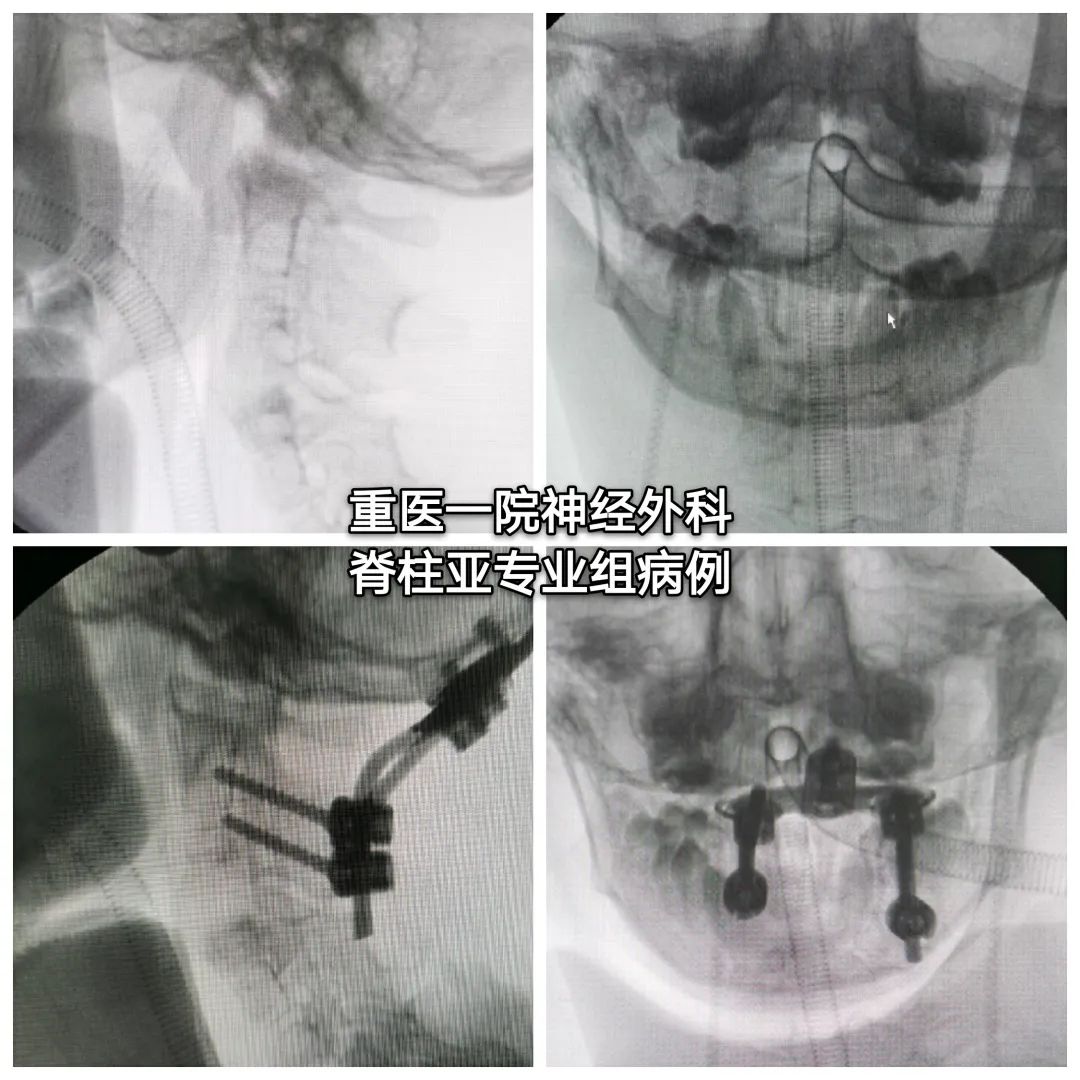

后路枕颈关节撑开矫形植骨融合内固定术

#术中情况#

#术后情况#

3、术中恢复缺如的右侧C1侧块高度,并在在关节间植骨,以纠正斜颈。